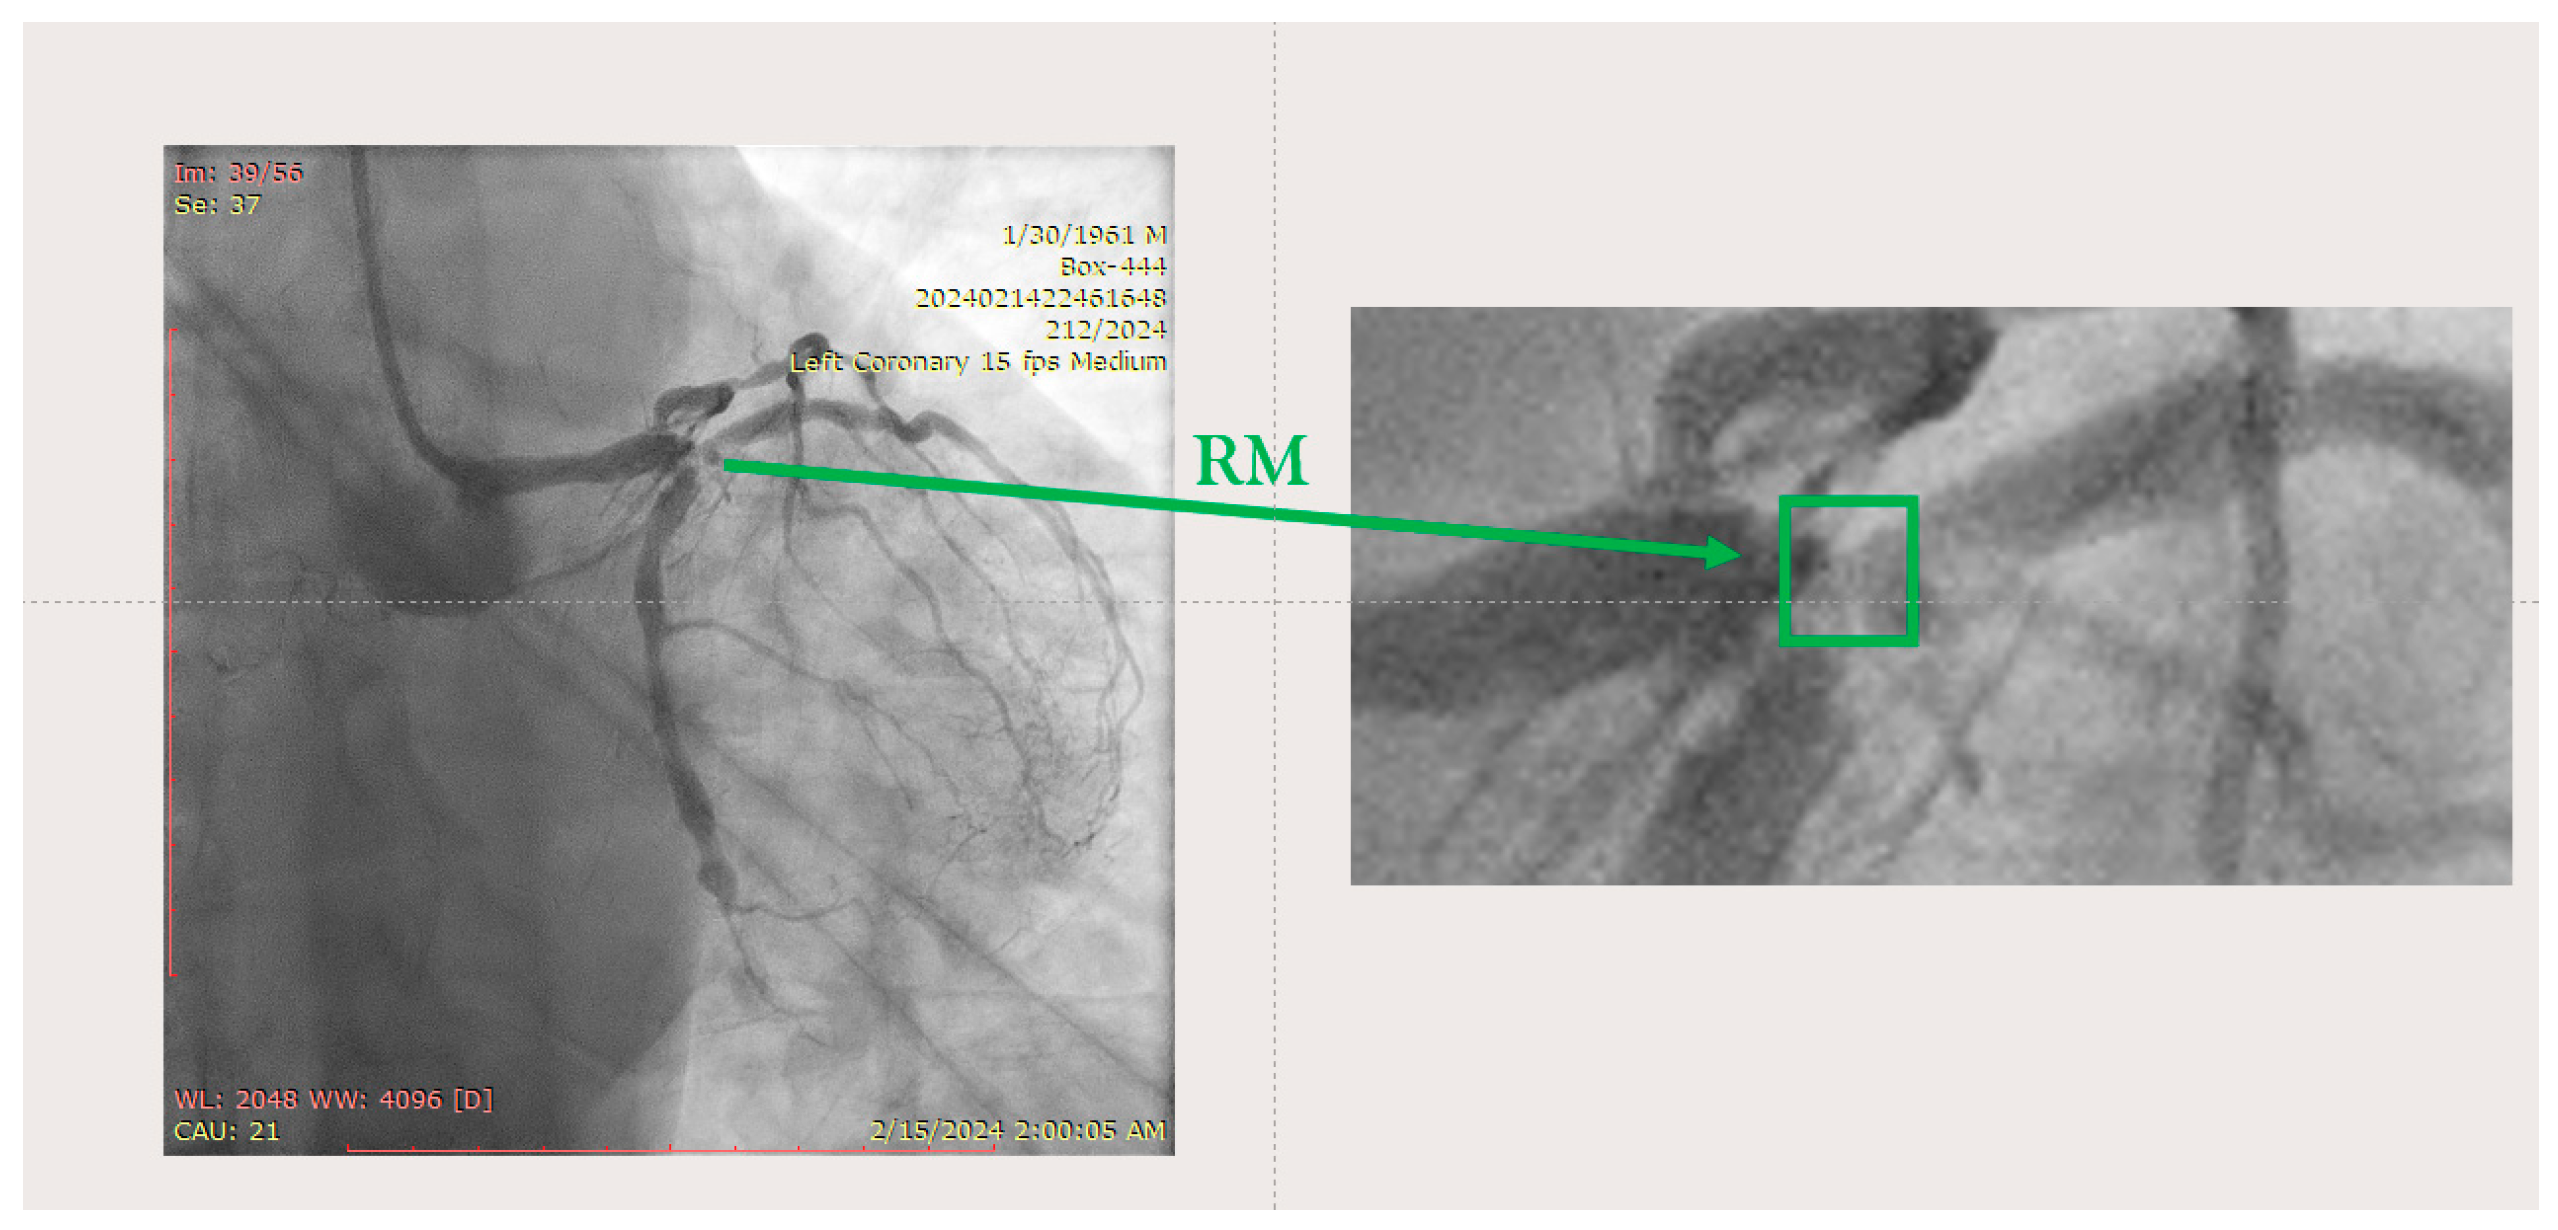

Figure 5.

Left coronary artery—RM(LAO caudal). Green arrow and square—ostium of RM.

The ostium of left anterior descending artery (LAD) presented a 75% stenotic lesion, with the proximal segment displaying a 90% lesion (Figure 3). The left circumflex artery (LCX) revealed a 75% stenotic lesion of the ostium and tapered disease of its distal segment with areas of ectasic disease, with the ostium of the ramus intermedius (RI/RM) showing a 75% lesion (modified Medina classification 0-1-1-1 [4]) (Figure 4, Figure 5, Figure 6, Figure 7, Figure 8, Figure 9 and Figure 10).